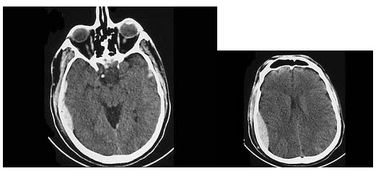

檢查顱腦和碟竇